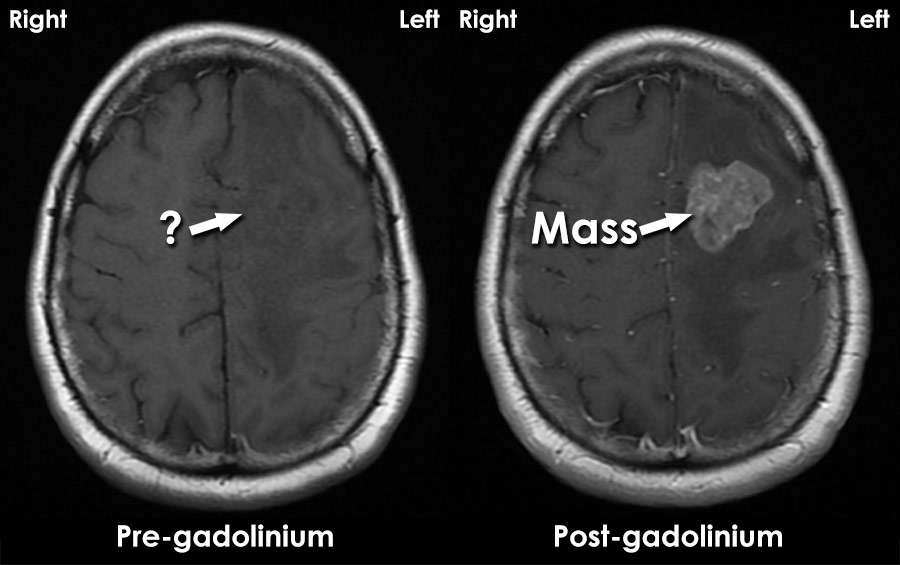

Gadolinium Contrast

https://www.radiologymasterclass.co.uk/images/mri/mri_gad.jpg?mtime=20210304211353&focal=none

MRIs And Contrast Gadolinium Powerful Patient

https://powerfulpatient.org/wp-content/uploads/2018/09/Screen-Shot-2015-10-26-at-8.51.12-PM.png